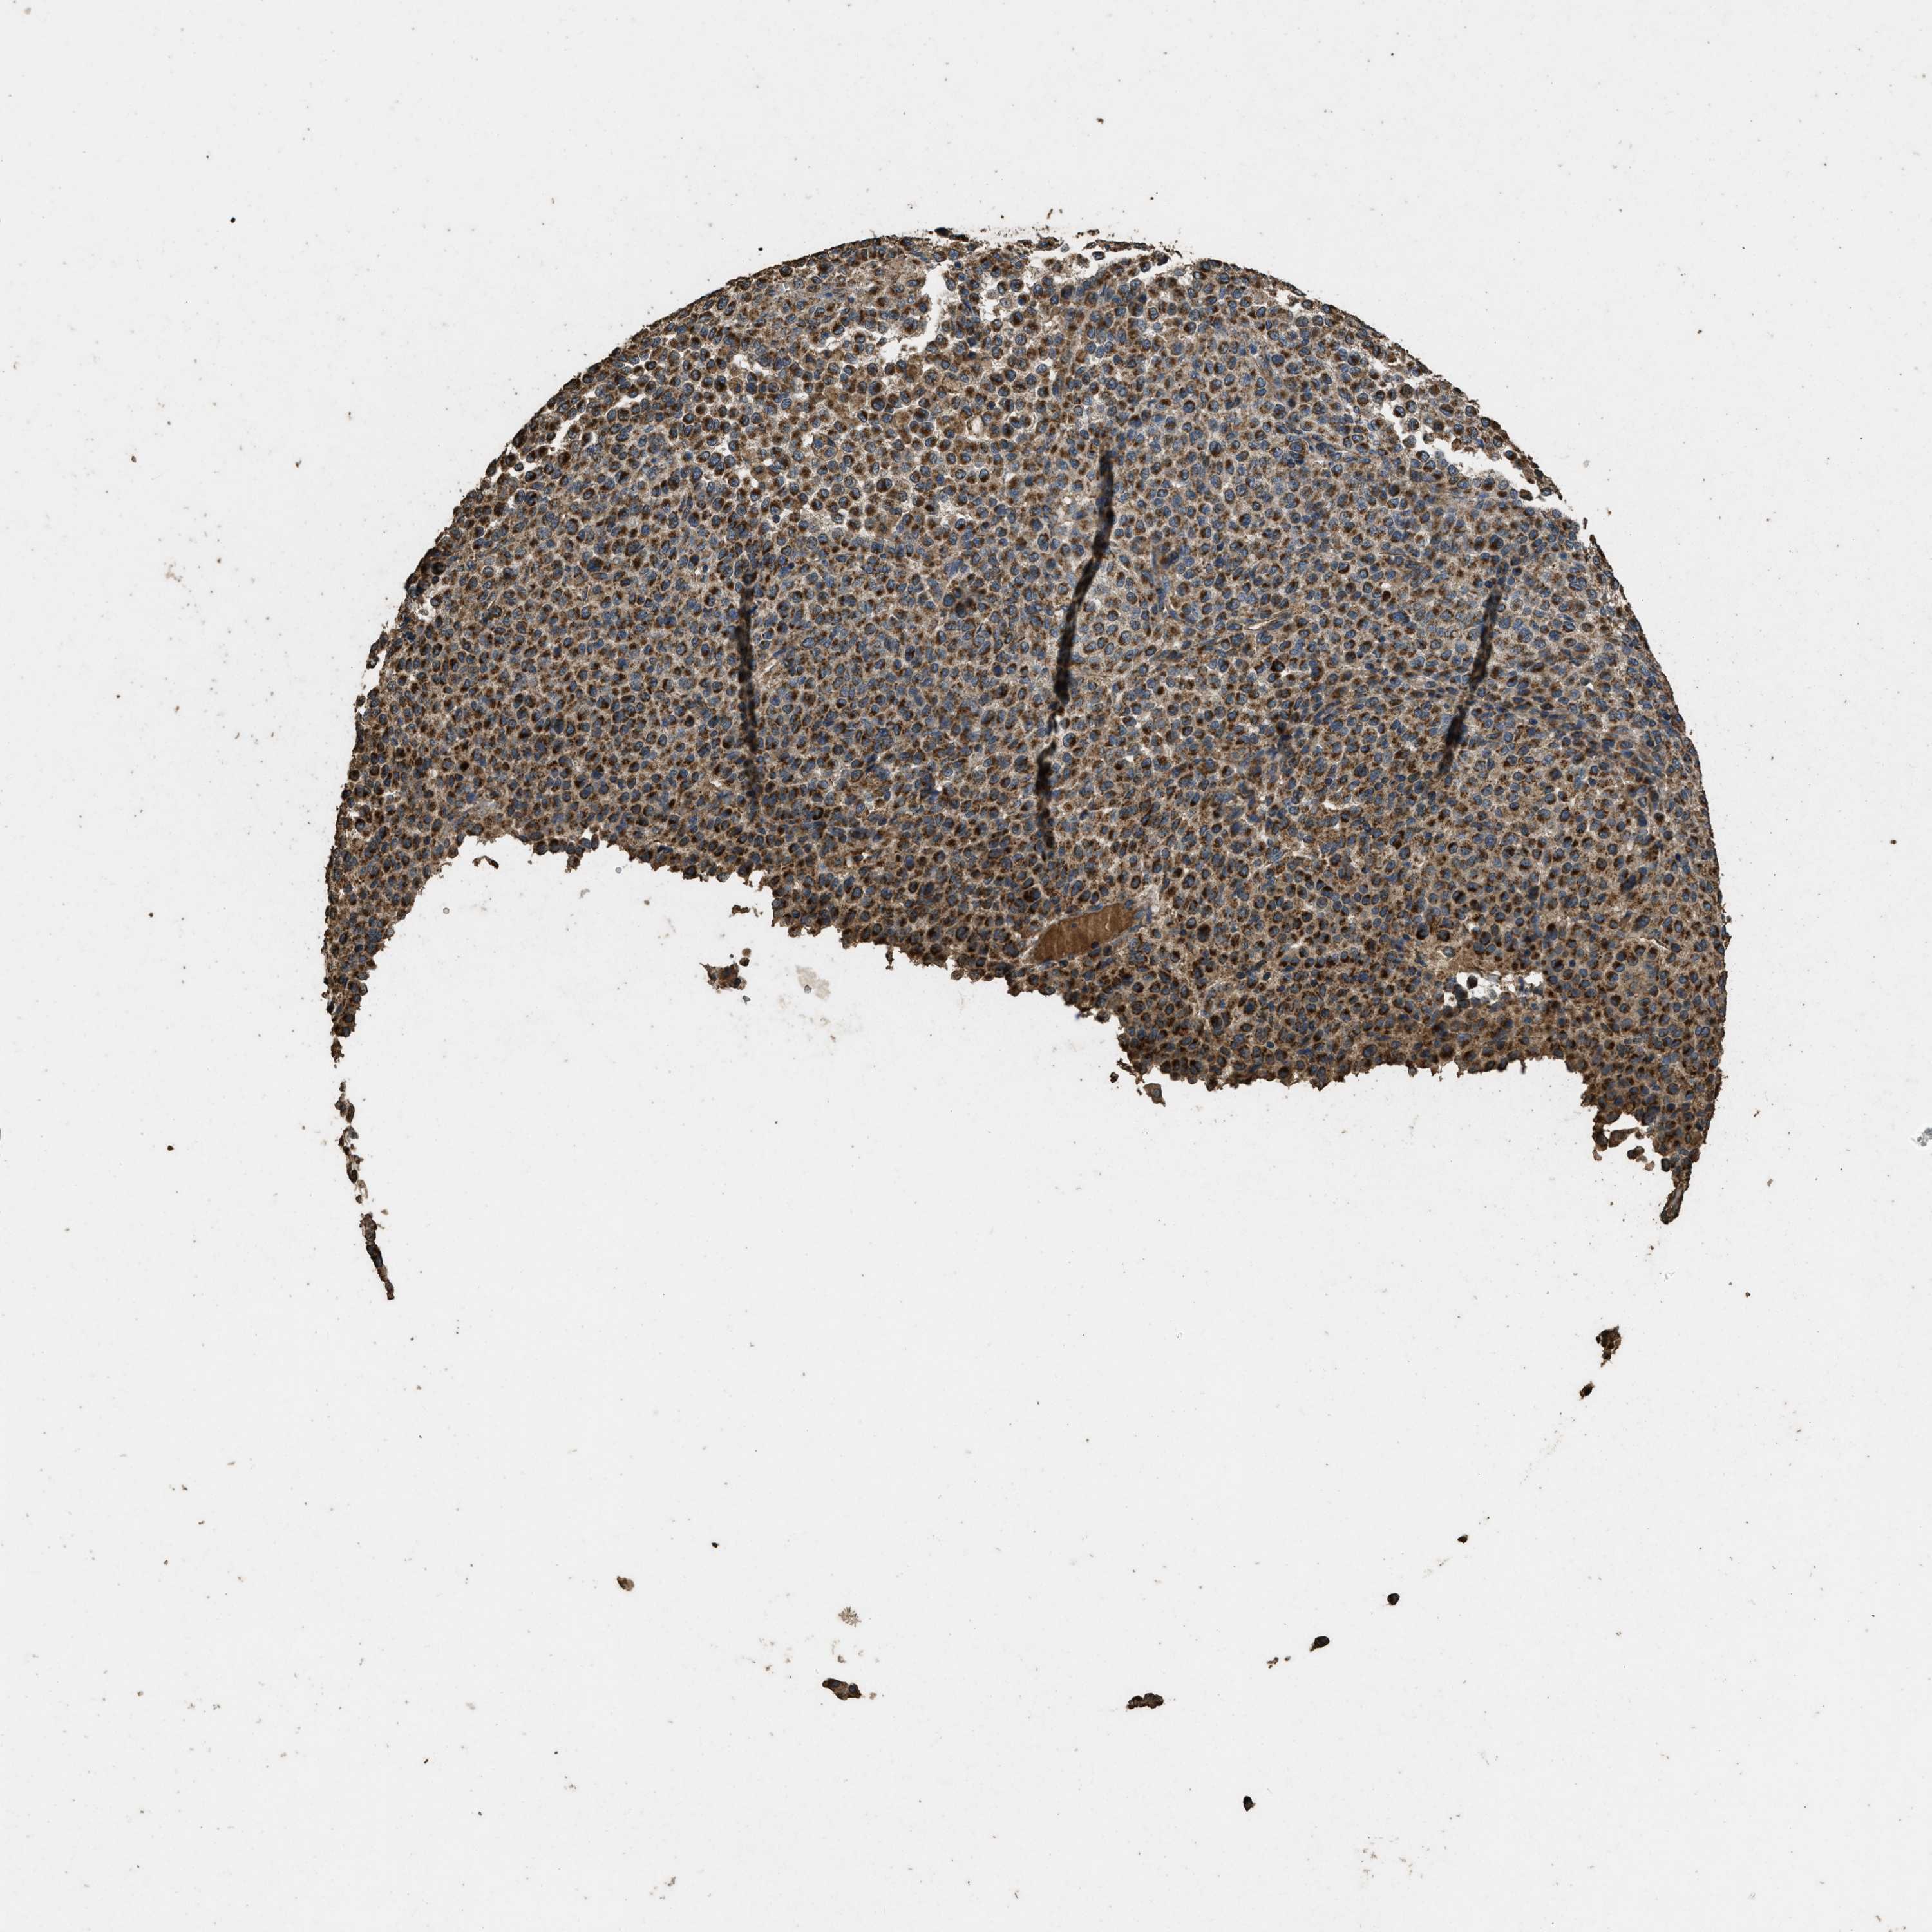

MELANOMA - Protein expressioni

A mouse-over function shows sample information and annotation data. Click on an image to view it in a full screen mode. Samples can be filtered based on level of antibody staining by selecting one or several of the following categories: high, medium, low and not detected. The assay and annotation is described here.

Note that samples used for immunohistochemistry by the Human Protein Atlas do not correspond to samples in the TCGA dataset.

Antibody stainingi

Antibody staining in the annotated cell types in the current human tissue is reported as not detected, low, medium, or high, based on conventional immunohistochemistry profiling in selected tissues. This score is based on the combination of the staining intensity and fraction of stained cells.

Each image is clickable and will lead to virtual microscopy that enables deeper exploration of all samples and also displays staining intensity scores, fraction scores and subcellular localization as well as patient and tissue information for each sample.

Antibody CAB017847

Staining

High

Medium

Low

Not detected

Intensity

Strong

Moderate

Weak

Negative

Quantity

>75%

75%-25%

<25%

None

Location

Nuclear

Cytoplasmic/membranous

Cytoplasmic/membranous,nuclear

Malignant melanoma, NOS

Malignant melanoma, Metastatic site